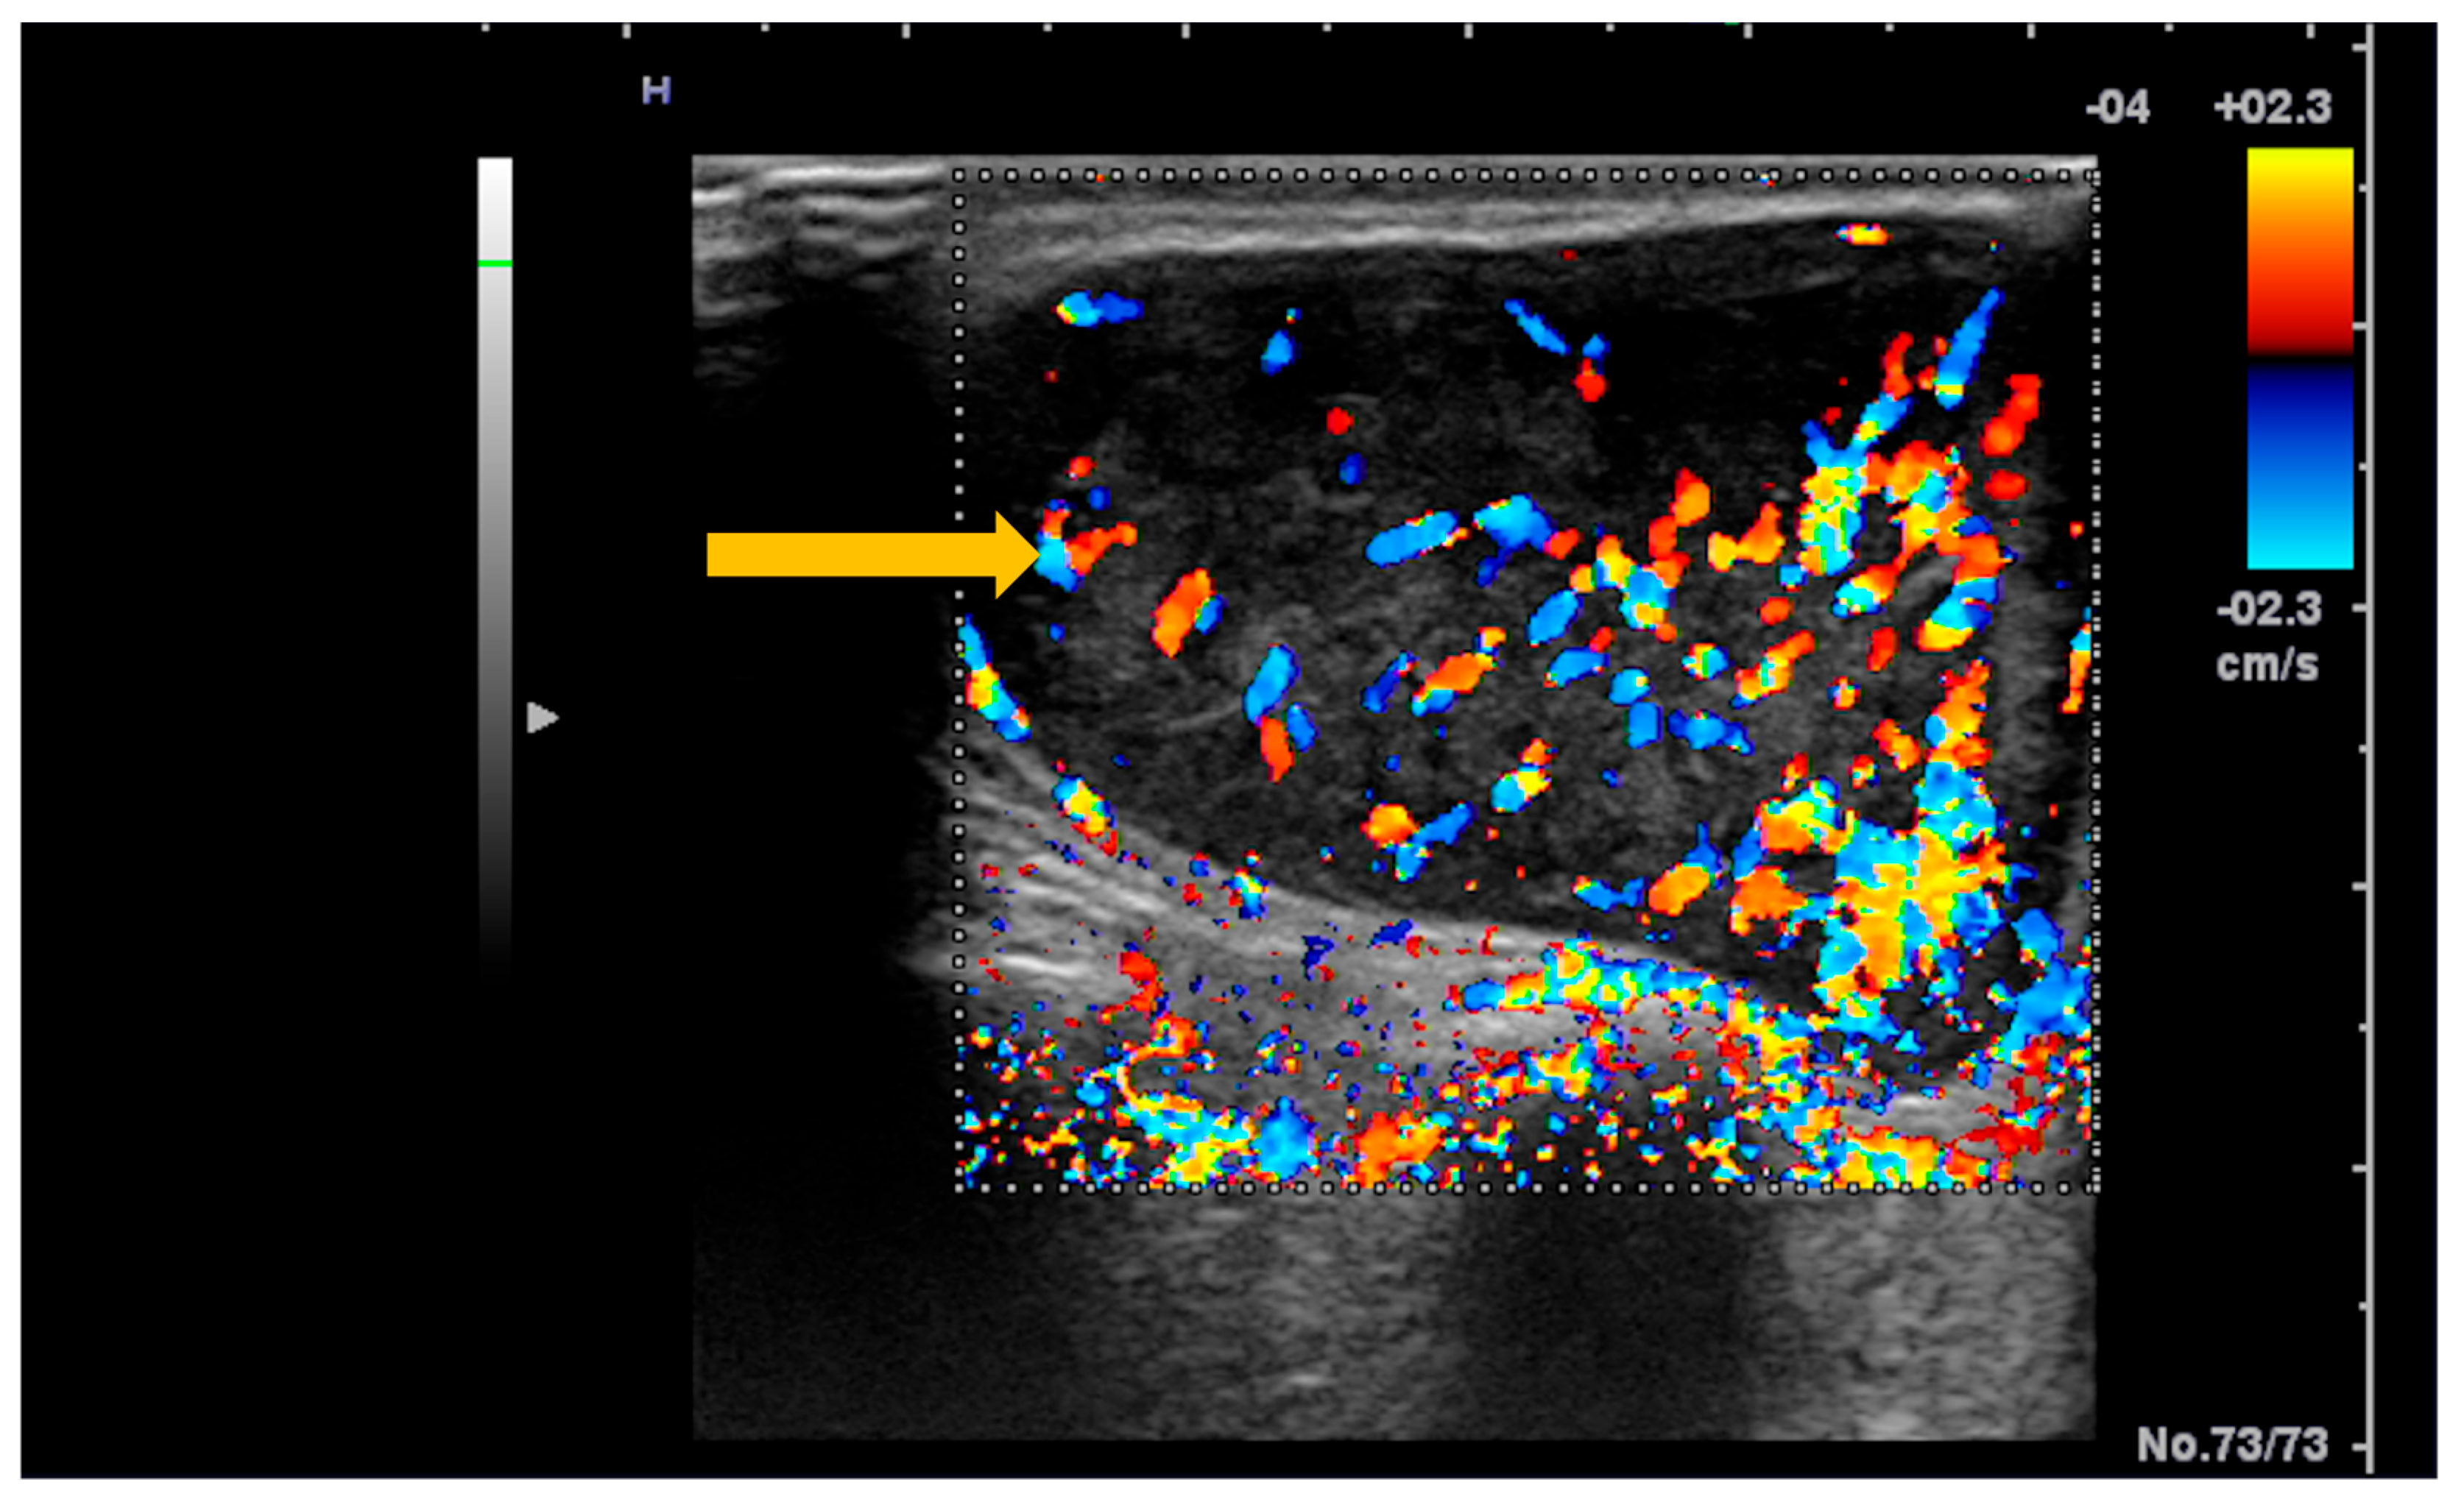

Elastography, both strain and shear-wave, provides additional information to conventional ultrasonography, demonstrating increased stiffness in the acute phase of myositis and reduced stiffness during disease progression, in the context of fatty infiltration (Figure 1) [35]. Because standardized reference values for normal muscle stiffness are not available in the literature, studies rely on comparisons between patients with Sjögren’s syndrome and healthy subjects. In patients with inclusion body myositis, muscle stiffness measured by shear-wave elastography (m/s) is lower compared with normal muscle: vastus lateralis (1.35 ± 0.32 vs. 1.68 ± 0.23), rectus femoris (1.52 ± 0.33 vs. 1.81 ± 0.23), vastus medialis (1.36 ± 0.16 vs. 1.60 ± 0.21) vastus intermedius (1.62 ± 0.49 vs. 1.86 ± 0.22), biceps femoris (1.30 ± 0.14 vs. 1.67 ± 0.20), semitendinosus (1.33 ± 0.31 vs. 1.66 ± 0.23), semimembranosus (1.36 ± 0.28 vs. 1.71 ± 0.18) (p < 0.05) [36].

Figure 1. Strain elastography and corresponding gray-scale imaging of myositis with fatty infiltration. Strain elastography of the thigh skeletal muscle demonstrates reduced tissue stiffness, as indicated by red color coding on the elastography map (thick arrow), indicating softening of the affected muscle. The corresponding gray-scale ultrasound image shows hyperechoic muscle texture (thin arrow), consistent with fatty infiltration.